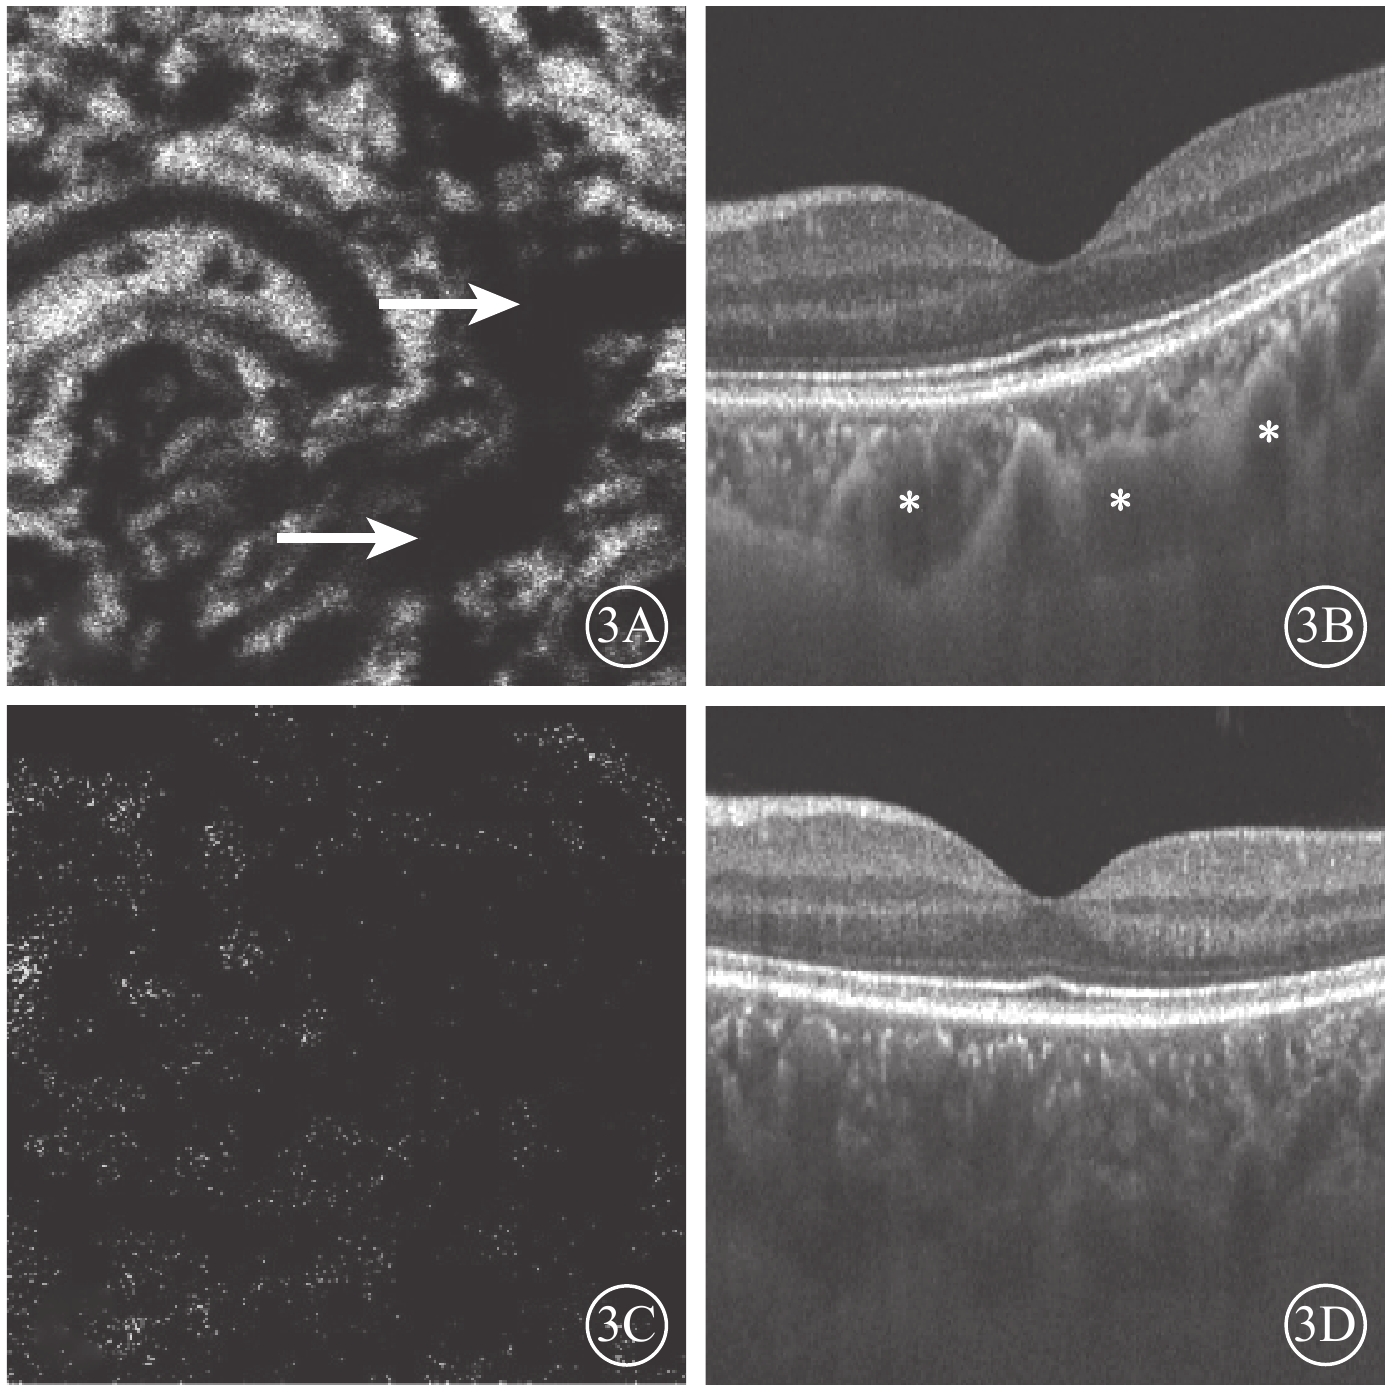

Bruch膜下1/2脈絡膜厚度層面,SS-OCTA圖像呈現與平面(en-face)OCT所示脈絡膜大血管分布較為一致的黑色血流信號,經二值化處理后所得的黑白圖像能反映脈絡膜大血管層的高速血流分布(圖2)。ECS組受檢眼脈絡膜SS-OCT和脈絡膜大血管層SS-OCTA表現為個別脈絡膜大血管極度擴張、高速血流匯聚和脈絡膜大血管普遍擴張、高速血流彌漫分布兩種類型。13只眼中,個別脈絡膜大血管極度擴張、高速血流匯聚6只眼;脈絡膜大血管普遍擴張、高速血流彌漫分布7只眼(圖3),其中1只眼為漿液性脈絡膜視網膜病變。對照組受檢眼脈絡膜SS-OCT無明顯大血管擴張征象,脈絡膜大血管層SS-OCTA圖像顯示高速血流分散而細小(圖4)。ECS組、對照組受檢眼脈絡膜大血管層FBFD分別為(76.35±14.46)%、(63.57±13.42)%;兩組受檢眼脈絡膜大血管層FBFD比較,差異有統計學意義(t=2.775,P=0.01)。

圖3

ECS組黃斑區脈絡膜大血管層en-face SS-OCTA和B掃描圖。3A. en-face SS-OCTA,高速血流極度匯聚(白箭);3B. B掃描圖,脈絡膜個別大血管極度擴張(星號);3C. en-face血流圖像,高速血流彌漫分布;3D. B掃描圖,脈絡膜大血管普遍擴張

圖3

ECS組黃斑區脈絡膜大血管層en-face SS-OCTA和B掃描圖。3A. en-face SS-OCTA,高速血流極度匯聚(白箭);3B. B掃描圖,脈絡膜個別大血管極度擴張(星號);3C. en-face血流圖像,高速血流彌漫分布;3D. B掃描圖,脈絡膜大血管普遍擴張

Bruch膜下1/2脈絡膜厚度層面,SS-OCTA圖像呈現與平面(en-face)OCT所示脈絡膜大血管分布較為一致的黑色血流信號,經二值化處理后所得的黑白圖像能反映脈絡膜大血管層的高速血流分布(圖2)。ECS組受檢眼脈絡膜SS-OCT和脈絡膜大血管層SS-OCTA表現為個別脈絡膜大血管極度擴張、高速血流匯聚和脈絡膜大血管普遍擴張、高速血流彌漫分布兩種類型。13只眼中,個別脈絡膜大血管極度擴張、高速血流匯聚6只眼;脈絡膜大血管普遍擴張、高速血流彌漫分布7只眼(圖3),其中1只眼為漿液性脈絡膜視網膜病變。對照組受檢眼脈絡膜SS-OCT無明顯大血管擴張征象,脈絡膜大血管層SS-OCTA圖像顯示高速血流分散而細小(圖4)。ECS組、對照組受檢眼脈絡膜大血管層FBFD分別為(76.35±14.46)%、(63.57±13.42)%;兩組受檢眼脈絡膜大血管層FBFD比較,差異有統計學意義(t=2.775,P=0.01)。

圖3

ECS組黃斑區脈絡膜大血管層en-face SS-OCTA和B掃描圖。3A. en-face SS-OCTA,高速血流極度匯聚(白箭);3B. B掃描圖,脈絡膜個別大血管極度擴張(星號);3C. en-face血流圖像,高速血流彌漫分布;3D. B掃描圖,脈絡膜大血管普遍擴張

圖3

ECS組黃斑區脈絡膜大血管層en-face SS-OCTA和B掃描圖。3A. en-face SS-OCTA,高速血流極度匯聚(白箭);3B. B掃描圖,脈絡膜個別大血管極度擴張(星號);3C. en-face血流圖像,高速血流彌漫分布;3D. B掃描圖,脈絡膜大血管普遍擴張